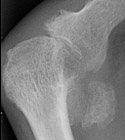

OA - - Osteoarthritis: Joint space narrowing and Osteophytes at 1st MTP joint

+++